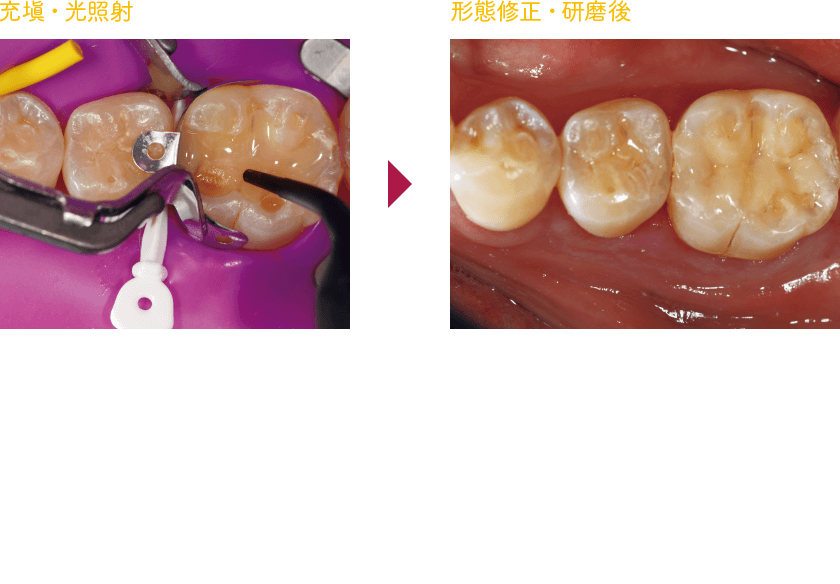

基本ステップ(コンポジットレジン修復)